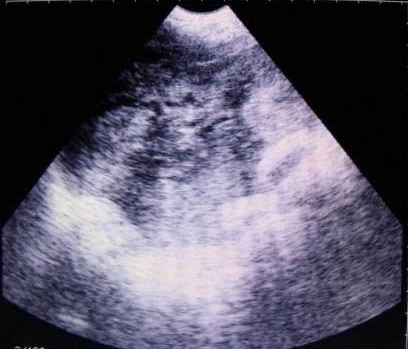

獸用B超機檢測母豬有胎兒圖像

豬用B超機檢測有胎兒圖像